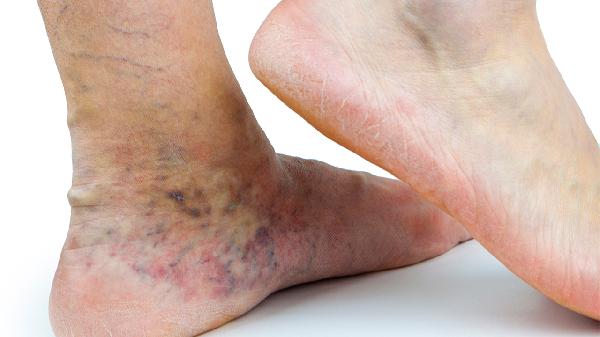

颞颌关节炎可遵医嘱使用布洛芬缓释胶囊、双氯芬酸钠缓释片、硫酸氨基葡萄糖胶囊、盐酸乙哌立松片、塞来昔布胶囊等药物。颞颌关节炎可能与关节损伤、咬合异常、免疫因素、感染或精神紧张等因素有关,通常表现为关节区疼痛、张口受限、弹响等症状。